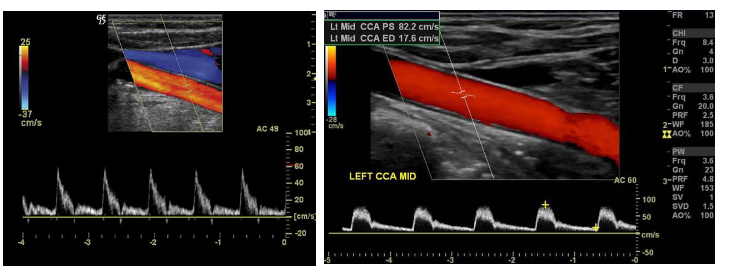

STRUMENTAZIONE IN USO presso lo studio Tilocca ESAOTE MY LAB TWICE 2019CRYSTAL LINE HD technology

• ECO COLOR DOPPLER TSA ( VASI DEL COLLO)